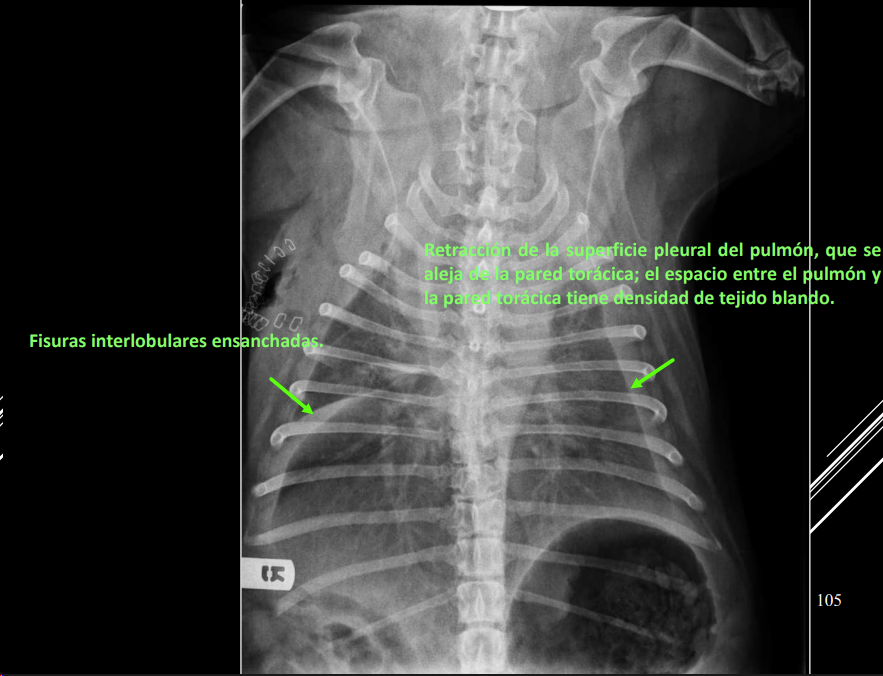

Derrame pleural

- Líquido en espacio pleural (uni/bilateral).

- RX:

Neumotórax